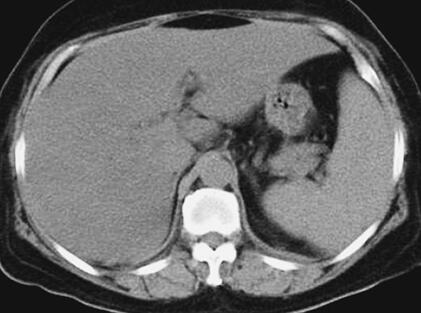

患者,女性,59岁。因“发热8天,上腹部隐痛、腹泻伴胸闷7天”于2011年7月8日入院。患者8天前出现发热,39.5℃,无畏寒、寒战,在当地卫生院予输液治疗(具体不详),症状未好转。7天前出现上腹部隐痛、腹泻,日约4~5次,黄色稀便,伴胸闷,遂就诊于当地镇医院,心电图检查正常,拟“中暑”,予针灸等治疗后无好转。2天前就诊于当地县人民医院,查血常规:WBC 8.4×109/L,N 89.2%,Hb 102g/L,PLT 92×109/L;肥达反应阴性;肝功能:ALT 104IU/L,AST 144IU/L,TP 55g/L,ALB 27g/L;腹部CT:脂肪肝,脾肿大;胸部CT:两肺少许炎症,左侧可疑少许胸腔积液,拟败血症,中毒性肝炎,伤寒住院治疗;期间体温波动于38~39℃,血压波动于80/50~90/60mmHg,予多巴胺[6.0μg/(kg·min)]升压,予亚胺培南-西司他汀钠联合头孢曲松抗感染治疗,病情无好转,仍有发热、腹泻、上腹部隐痛不适,并出现尿量减少、血肌酐升高。于7月8日转笔者医院急诊,测血压[多巴胺6.0μg/(kg·min)维持]89/55mmHg,血常规:WBC 10.28×109/L,N 89.4%;Lac 2.3mmol/L,CRP>90.0mg/L,Cr 141μmol/L,cTnI 6.02μg/L,BNP 577pg/ml;胸腹部CT:两下肺背侧散在炎症,两侧胸腔少量积液,慢肝样病变,胆囊结石(图1、图2);腹部B超:脂肪肝,脾偏大,拟发热待查,心肌炎?感染性休克?,予补液、亚胺培南-西司他汀钠控制感染,多巴胺升血压,为进一步治疗拟上述诊断收入急诊重症监护病房。既往史:40年前发现胆囊结石。

图2 胸腹部CT:脾肿大(7月8日)